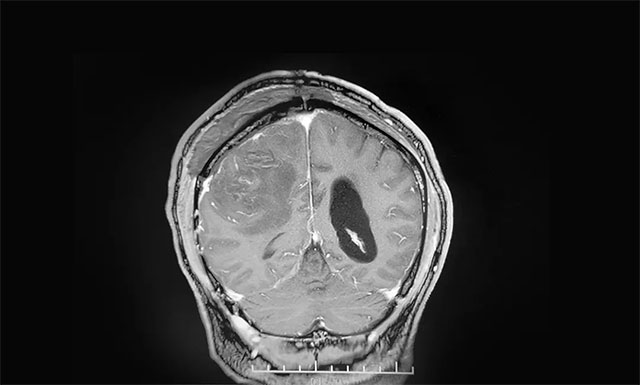

▲ 術(shù)后影像顯示腫瘤被切除

術(shù)后,患者手術(shù)恢復(fù)良好,未出現(xiàn)偏癱、失語等,左側(cè)肢體麻木消失,肢體活動較之前明顯改善,說話較之前流利許多。目前患者還在康復(fù)中,再過一段時間即可出院。